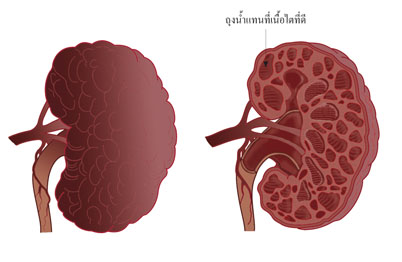

พบว่ามีถุงน้ำหรือซีสต์ (cyst) อยู่ในเนื้อไต ซีสต์จะงอกโตขึ้นเรื่อย ๆ จากเนฟรอนและขยายเบียดเนื้อไตที่ดีทำให้ไตเสื่อมและกลายเป็นโรคไตเรื้อรังมักพบในผู้ที่มีอายุตั้งแต่ ๓๐-๕๐ ปี อาการแสดงคือ มีอาการปวดหลัง บางครั้งคลำพบก้อนในท้อง มีการอักเสบติดเชื้อของทางเดินปัสสาวะบ่อย ๆ ปัสสาวะมีเลือดปน มีความดันโลหิตสูง โรคนี้ถ่ายทอดทางพันธุกรรมได้ดังนั้นจึงควรให้สมาชิกในครอบครัวตรวจปัสสาวะและถ่ายภาพเอกซเรย์ไตด้วย